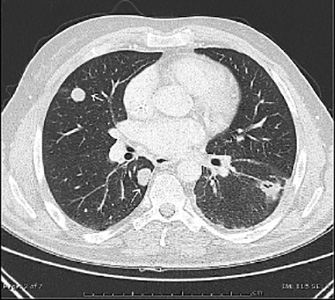

Nach Chemotherapie, im Besonderen bei Hodentumoren, können Läsionen als sog. sterilisierte Metastasen zurückbleiben. Histologisch enthalten diese Formationen im günstigsten Fall Fibrose und Nekrose in Abwesenheit vitaler Tumorzellen (Abb. 1).

Abb.1 Lungenmetastasen eines nicht seminomatösen Hodentumors (Z.n. Chemotherapie). Die Computertomographie zeigt zwei solide Herdbefunde rechts (Segment 5 und 6) sowie eine einzelne Metastase mit zentraler Einschmelzung im linken Unterlappen (Segment 6)